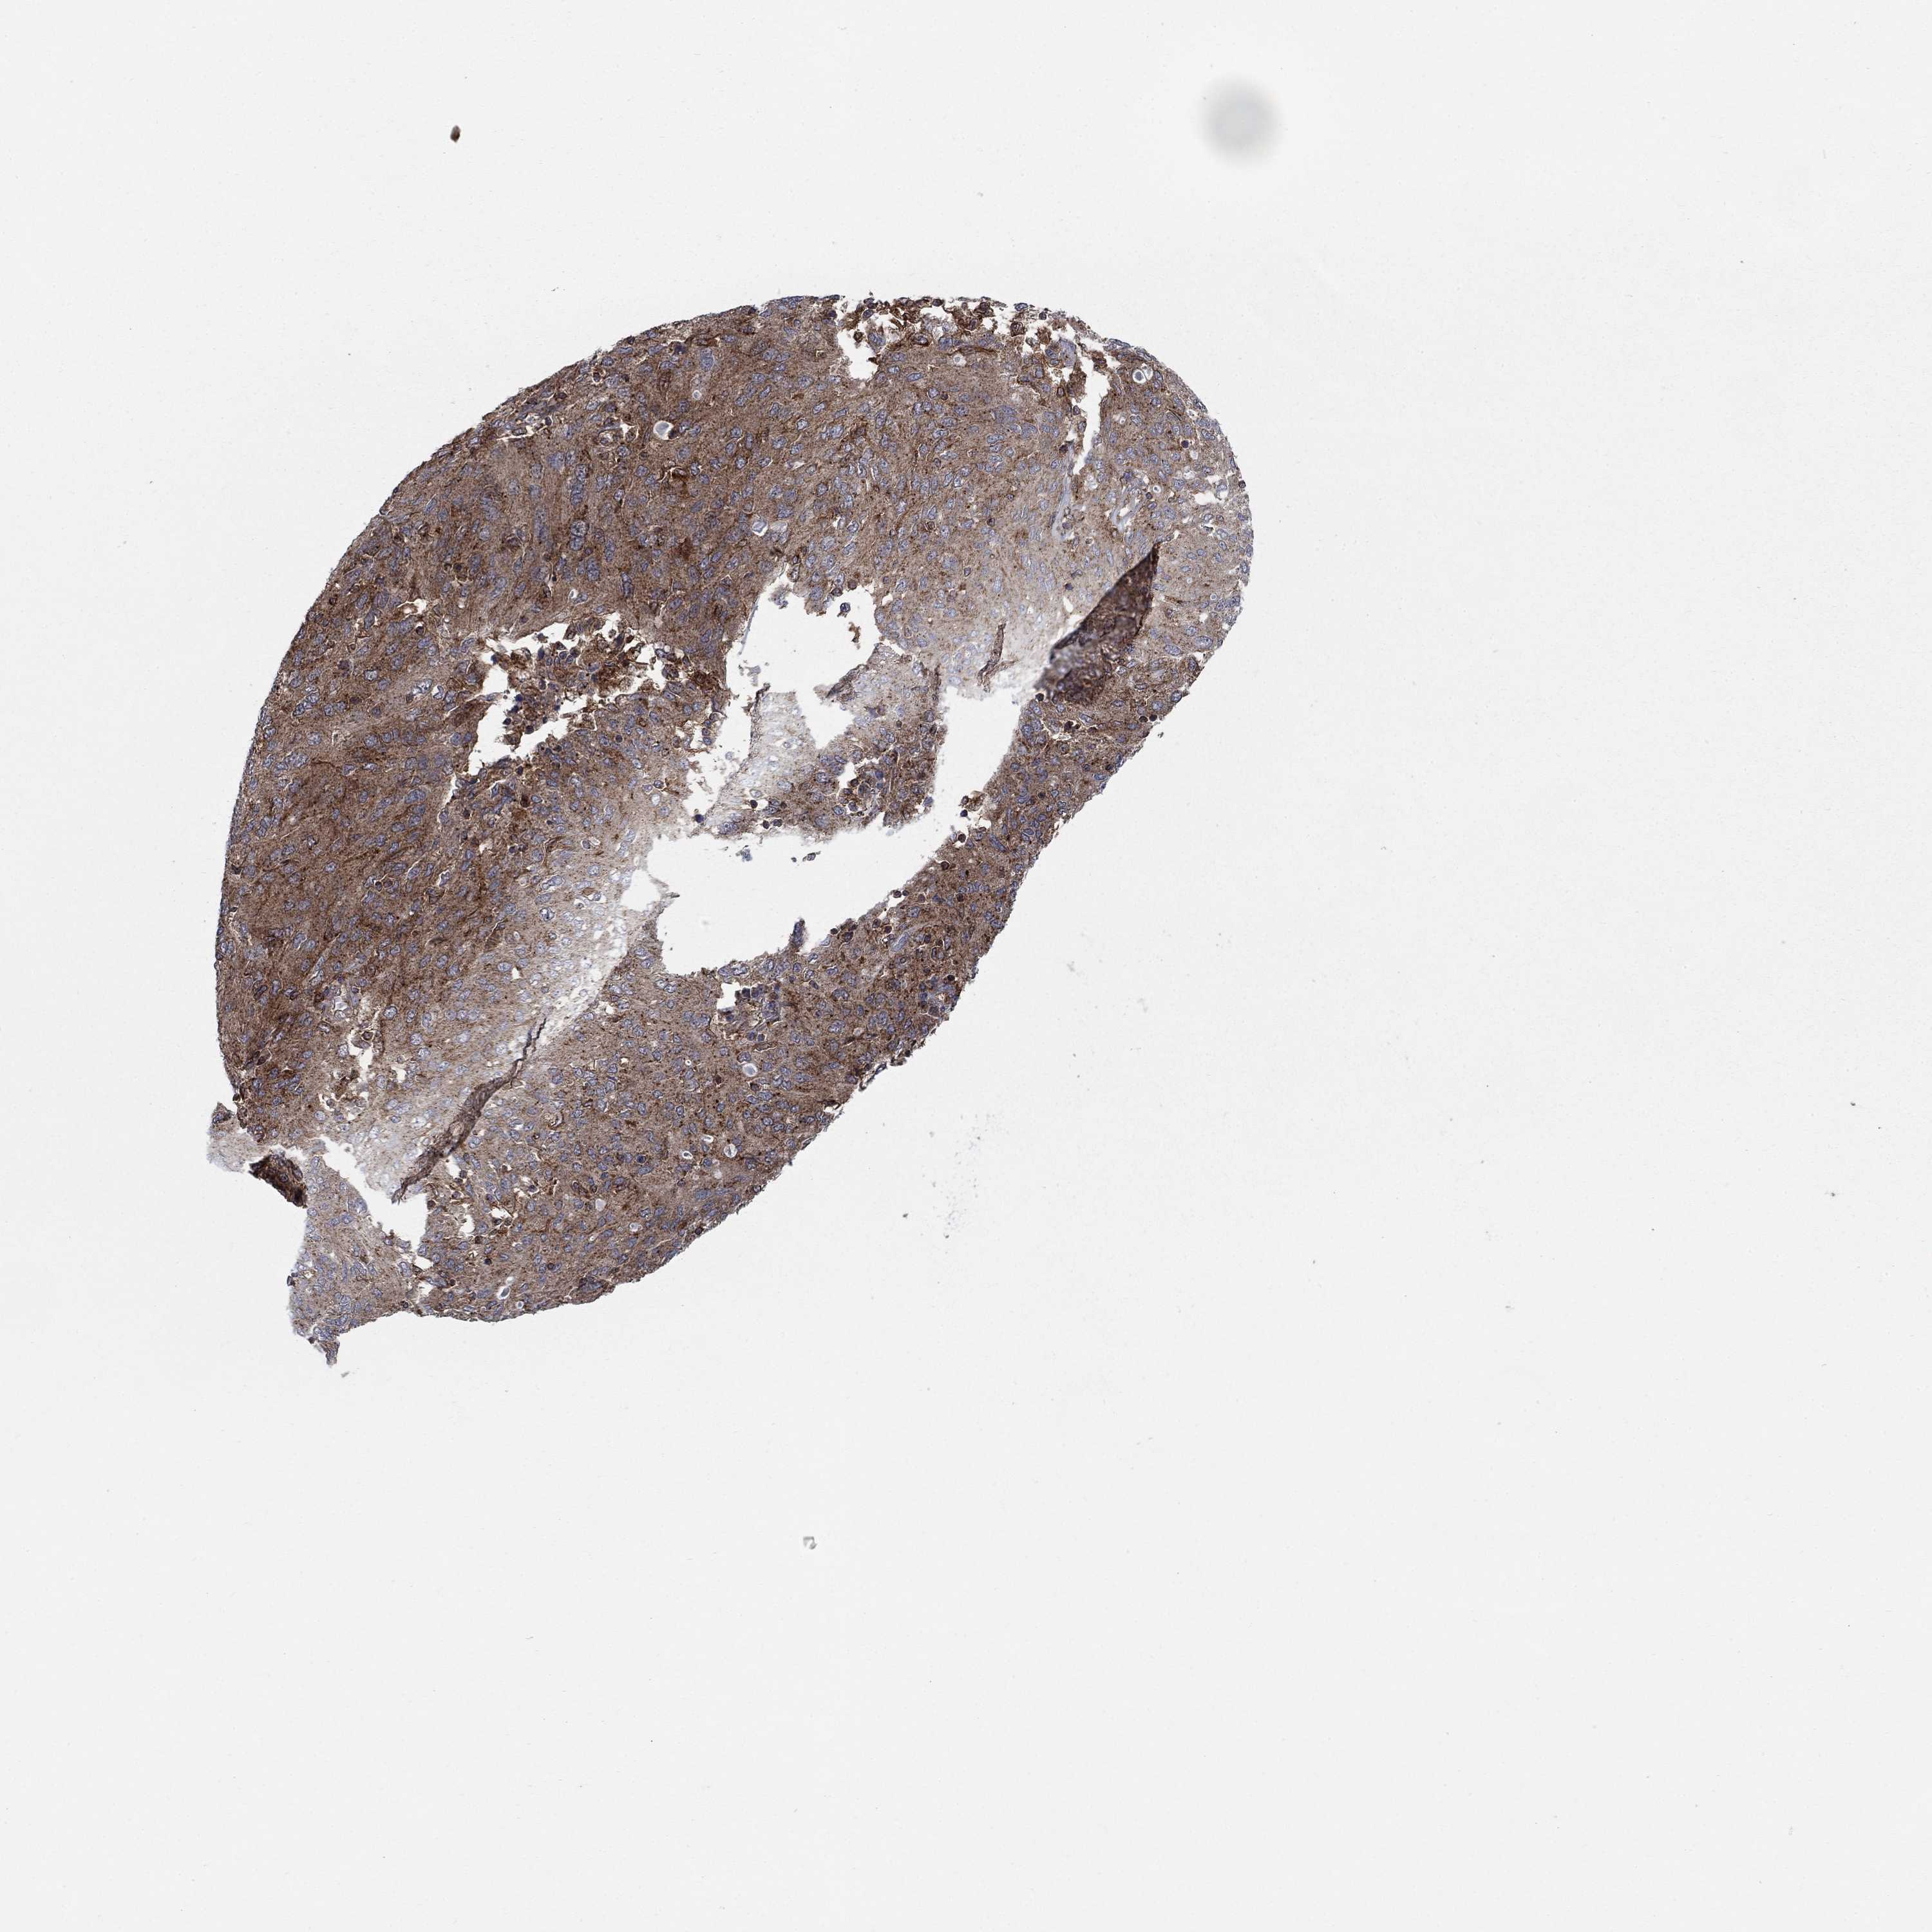

OVARIAN CANCER - Protein expressioni

A mouse-over function shows sample information and annotation data. Click on an image to view it in a full screen mode. Samples can be filtered based on level of antibody staining by selecting one or several of the following categories: high, medium, low and not detected. The assay and annotation is described here.

Note that samples used for immunohistochemistry by the Human Protein Atlas do not correspond to samples in the TCGA dataset.

Antibody stainingi

Antibody staining in the annotated cell types in the current human tissue is reported as not detected, low, medium, or high, based on conventional immunohistochemistry profiling in selected tissues. This score is based on the combination of the staining intensity and fraction of stained cells.

Each image is clickable and will lead to virtual microscopy that enables deeper exploration of all samples and also displays staining intensity scores, fraction scores and subcellular localization as well as patient and tissue information for each sample.

Antibody HPA075580

Staining

High

Medium

Low

Not detected

Intensity

Strong

Moderate

Weak

Negative

Quantity

>75%

75%-25%

<25%

None

Location

Nuclear

Cytoplasmic/membranous

Cytoplasmic/membranous,nuclear

Cystadenocarcinoma, serous, NOS

Cystadenocarcinoma, mucinous, NOS

Carcinoma, endometroid